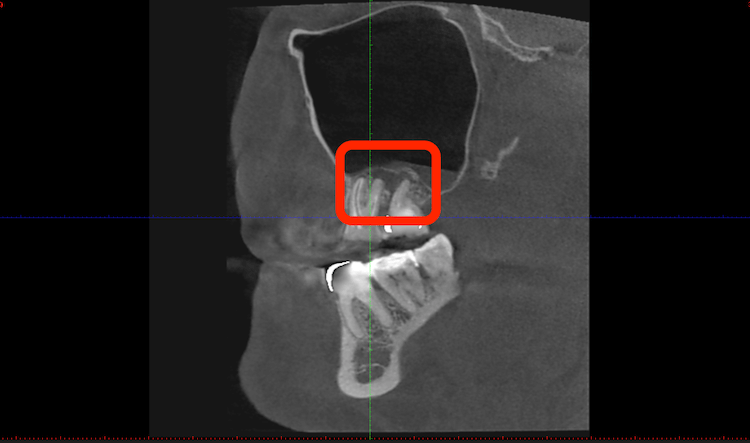

Повторная КТ диагностика. Постоянное протезирование

Спустя несколько месяцев после лечения, на новом КТ снимке обнаружили полноценное завершение процесса заживления в тех местах, где локализовались кистогранулемы.